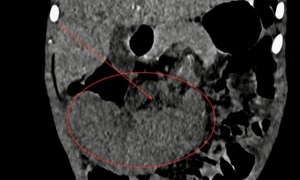

Việt kiều Mỹ 73 tuổi lựa chọn về Việt Nam phẫu thuật khối u đại tràng ác tính

Camera bệnh viện - 10/10/2025 14:55SKĐS - Việt kiều Mỹ 73 tuổi quyết định đến Bệnh viện Đa khoa Thủ Đức để thăm khám sau khi xuất hiện các dấu hiệu bất thường về đường tiêu hóa. Kết quả phát hiện khối u đại tràng ác nên nhanh chóng được phẫu thuật cắt bỏ.